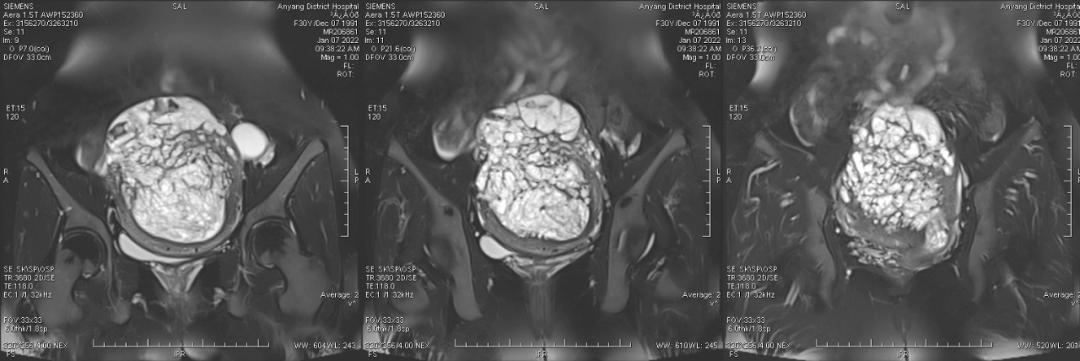

病例二

女,30 岁,侵蚀性葡萄胎,穿透宫壁全层。引道出血 20 多天,既往有 3 次人工流产病史。